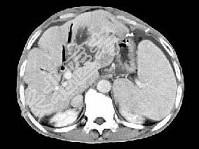

- 单项选择题根据所提供的图像,最可能的诊断是 ( )

A、肝囊肿

B、肝脓肿

C、肝胆管细胞癌伴肝硬化

D、肝细胞癌

E、以上都不是